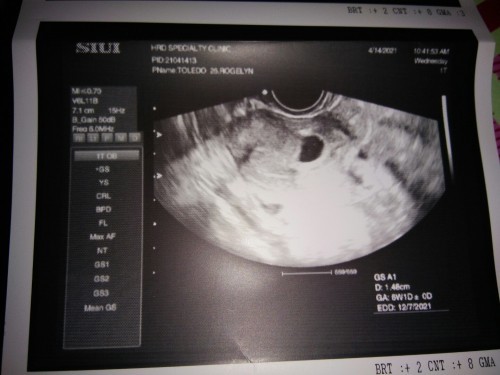

6.1weeks palang po akong buntis,, sa ultrasound po ba makikita na agad ang heartbeat ng baby? #advicepls #1sttimemom

nung sa akin 5weeks meron na po. case to case naman po yan, pray ka lang wag pa stress tapos take ka pa rin ng prenatal vitamins mo and milk. π

Yung case ko po is 7 weeks po nakitaan ng heartbeat si baby nun.